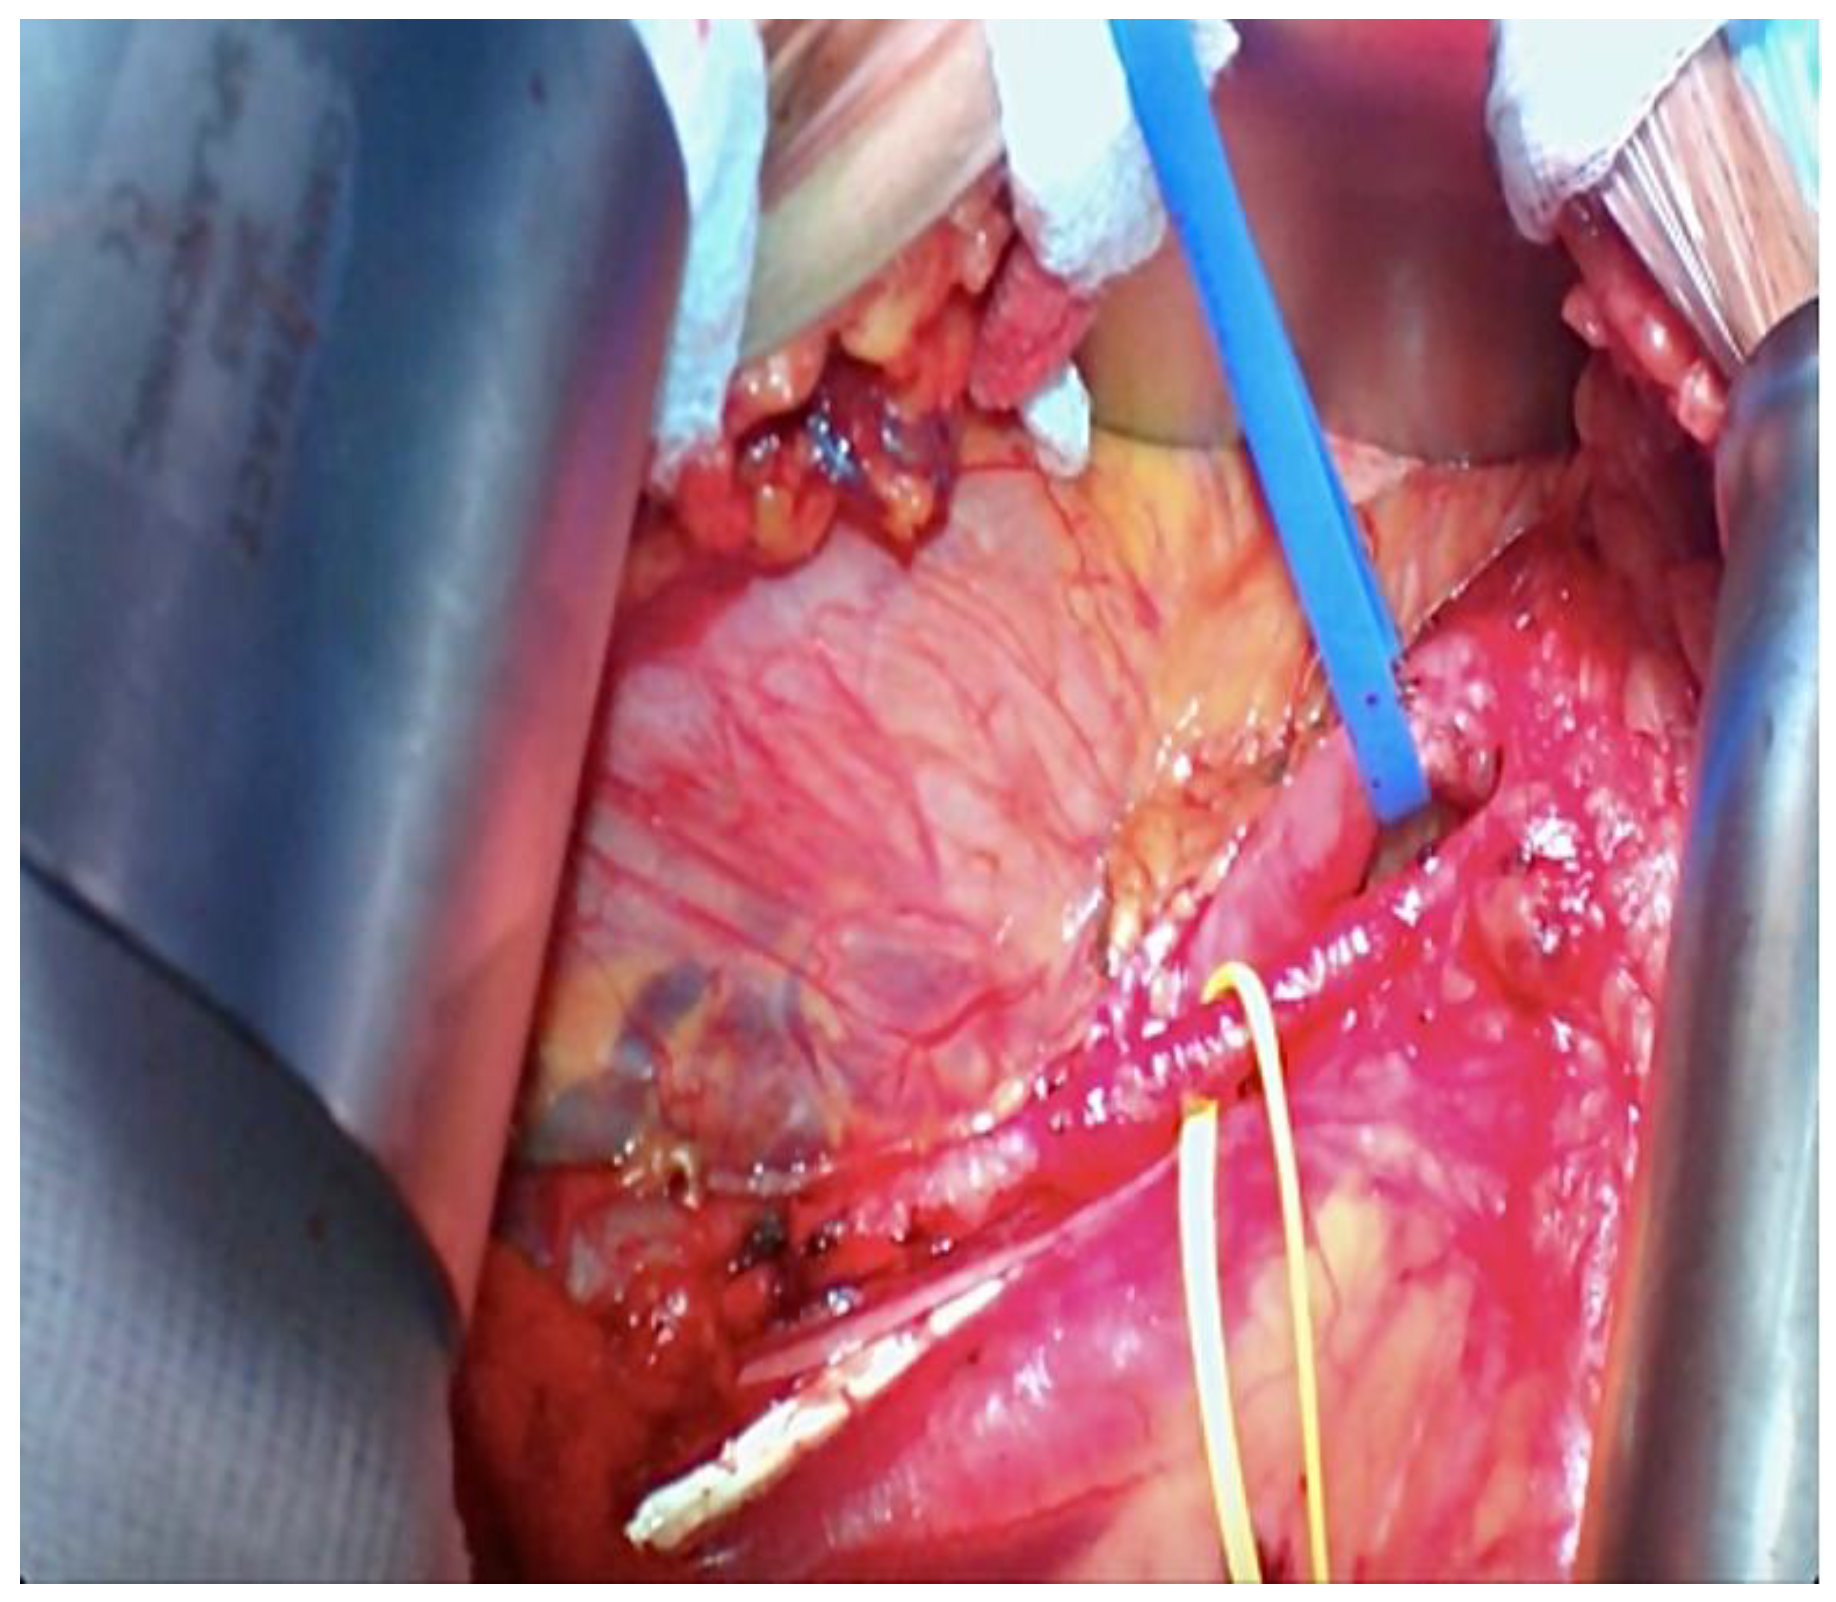

3. Methods and Procedure